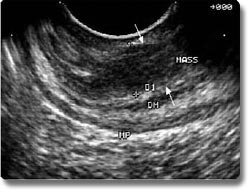

超声内镜检查是近年开发的一种直视性的腔内超声技术,超声探头位于内镜前端,可同时进行电子内镜和超声检查。由于超声探头距病变部位很近,且不受胃肠道气体的影响,能将粘膜下病变及其邻近器官的断层图像清晰地显示。主要用于电子内镜和体外超声等影像技术难以诊断的消化道粘膜下肿瘤的鉴别诊断、胃食管癌的病程分期(肿瘤侵润深度、有无周围淋巴结及邻近器官转移)及胰腺肿瘤、胆总管下端结石等疾病的诊断。在超声内镜的引导下,还可作穿刺活检及介入治疗。 |